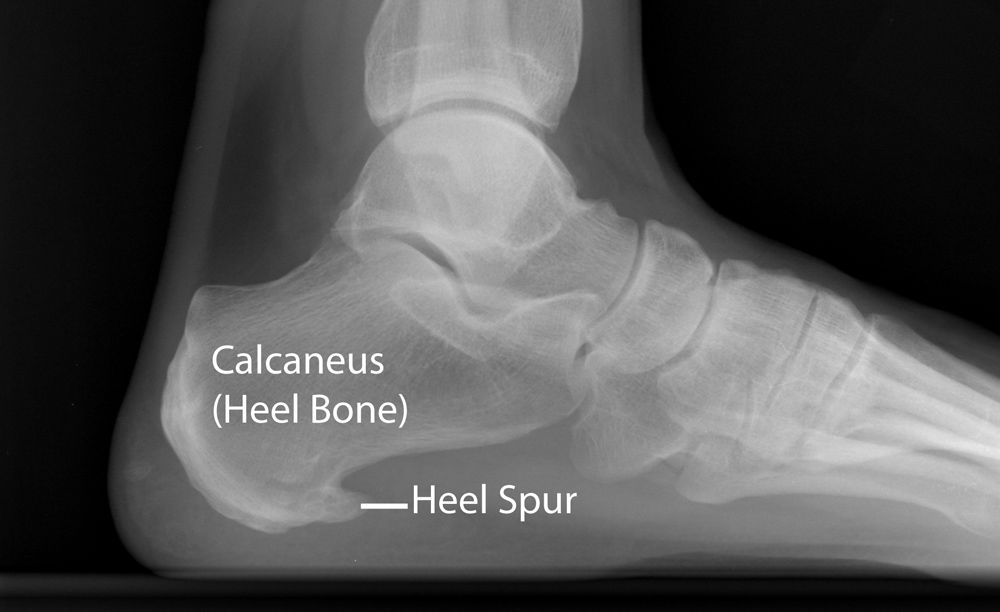

خارپاشنه نوعی التهابی است که در ناحیه کف پا و به خصوص در محل اتصال فاشیای پلانتار به استخوان پاشنه ایجاد میشود. این مشکل معمولاً باعث درد شدید در ناحیه پاشنه پا میشود که به خصوص در صبحها و یا بعد از استراحت طولانی مدت بیشتر احساس میشود.